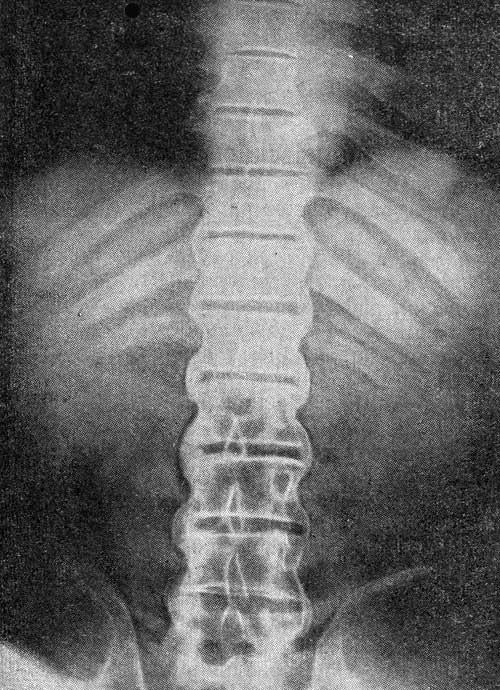

Дополнительной содержательной информацией для врача, служит подтверждение наследственного признака HLA-B27. Подтверждение общей диагностической гипотезы дает рентгенологическая информация, определяющая заметные изменения в крестцово-подвздошном сочленении.

Болезнь Бехтерева при правильном диагностировании имеет классификационные признаки.

| Классификация | Основные осложняющие признаки |

| Предположительная стадия | Рентгенологические снимки не дают подтверждения начала воспалительного процесса |

| Илиосакральная стадия | Начало поражения позвоночного сегмента |

| Стадия окостенения | Частичное окостенение определенного региона позвоночника |

| Поздняя стадия | Окостенение во всех трех (шейном, грудном и поясничном) отделах позвоночника |